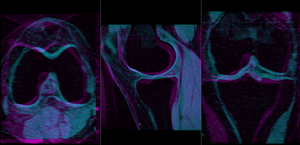

- check the result

- Place "MRI_58" in the background and "MRI_64" in the foreground

- switch to the Data module, locate the "MRI_64" node, and drag it onto the newly created "Xf1_Rigid" node.

- fade between background and foreground to judge the alignment.

- for better visibility, you can change the colormaps of the two volumes, as used in the examples shown here. Switch to the Volumes module, select "MRI_58" and then select "Green" from the Lookup Table menu. Similarly select "Cyan" for "MRI_64".

- check the result

- Place "MRI_58" in the background and "MRI_64" in the foreground

- switch to the Data module, locate the "MRI_64" node, and drag it onto the newly created "Xf1_Affine" node.

- fade between background and foreground to judge the alignment.

- for better visibility, you can change the colormaps of the two volumes, as used in the examples shown here. Switch to the Volumes module, select "MRI_58" and then select "Green" from the Lookup Table menu. Similarly select "Cyan" for "MRI_64".